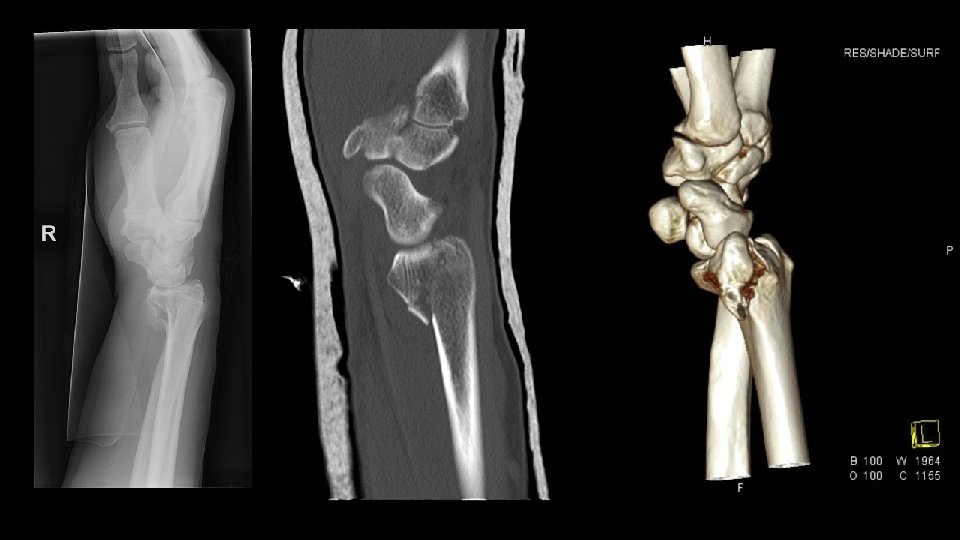

FX RADIOCUBITAL DISTAL FRACTURA DIE-PUNCH • Fx intraarticular de la carilla del radio que se articula con el semilunar. • Se produce por impactacion de semilunar contra el radio con depresion de la superficie articular. • Afectan al borde dorsal de la carilla mas que al volar.

FX RADIOCUBITAL DISTAL FRACTURA DIE-PUNCH